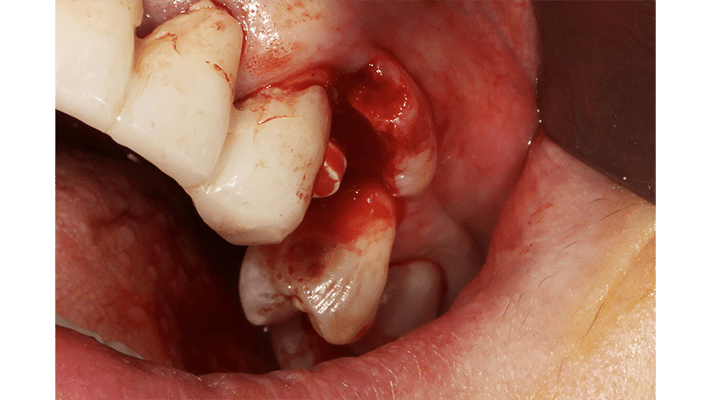

La situation clinique ci-contre illustre le temps par temps d’un rouleau réalisé lors d’un second temps chirurgical.

– Une première incision au contact osseux, légèrement déportée en palatin, au niveau estimé de la future limite du pilier de cicatrisation. La portion crestale, en regard de l’implant, sera la partie qui sera déportée en vestibulaire.

– Cette portion crestale est désépithélialisée, à lame froide ou à l’aide d’une fraise diamantée (comme si l’on avait pelé un fruit).

– Le lambeau est levé jusqu’en vestibulaire de l’implant afin de créer un espace pour la portion de tissu conjonctif en rotation.

– La portion crestale, toujours attachée au lambeau vestibulaire, est glissée en vestibulaire.

– Deux points en O simples sont réalisés et le tour est joué !